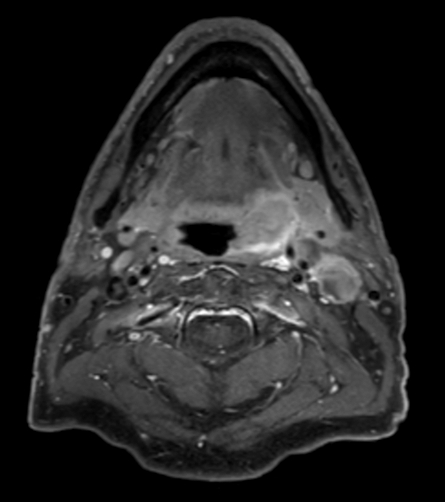

T1w TSE mDIXON (water only) post contrast

A 75-year-old male with oropharynx squamous cell carcinoma in the left tonsil region with extension into the soft palate, caudal border lower tonsil region, no midline crossing. On the left side in the neck there are also three enlared lymph nodes on level 2 and 3 with central necrosis and signs of limited extracapsular extensionn, T2N2b. Patient underwent MRI simulation in the radiotherapy (5-point) positioning mask in Ingenia MR-RT 3.0T using the Flex coils in combination with integrated Posterior FlexCoverage coil.